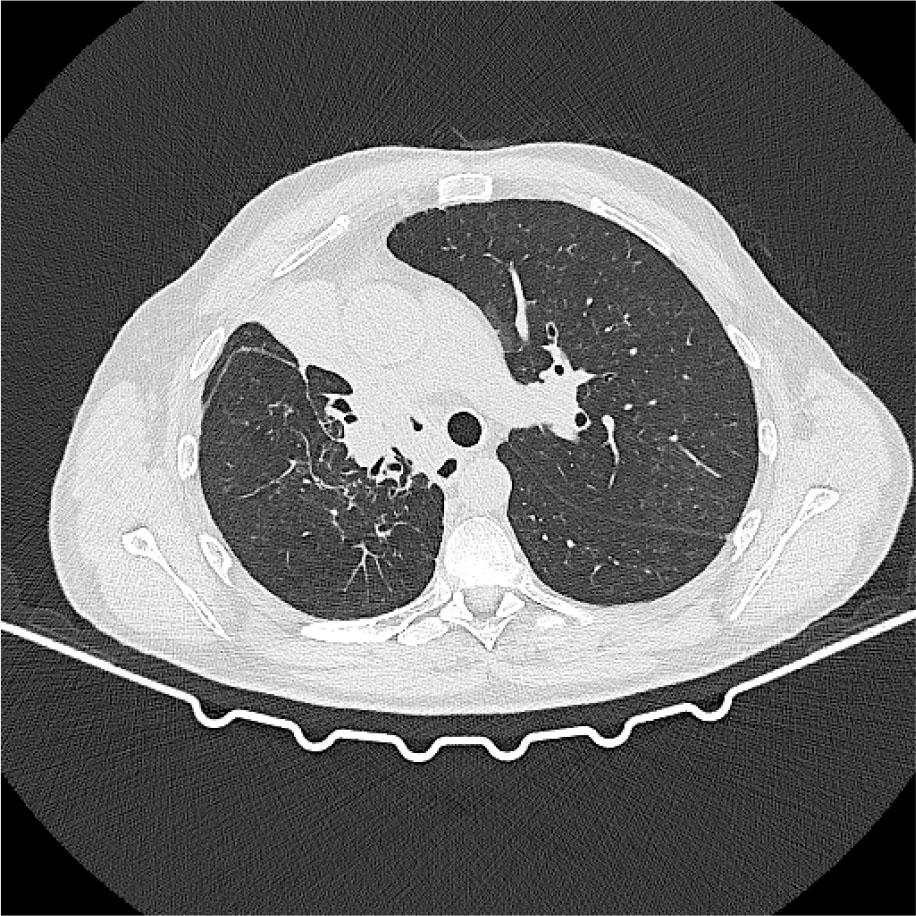

In September 2022, the patient complained of dyspnea on exertion and a dry cough for 2 weeks prior. A CT scan showed scattered ground-glass opacities in the left lung (figure 2). Amivantamab was suspended, and a bronchoalveolar lavage was performed, which showed alveolar lymphocytosis. The microbiologic examination identified Streptococcus pneumoniae, and antibiotic therapy was initiated. Imaging reassessment about 3 weeks later showed persistence of the lung opacities. A grade 2 CTCAE pneumonitis was assumed, and corticosteroid therapy with prednisolone 1 mg/kg was started. The patient reported improvement of symptoms, and a CT scan was performed after 5–6 weeks, which showed complete resolution of the radiologic abnormalities (figure 3).

CT scan after corticosteroid treatment showing resolution of the previous opacities.